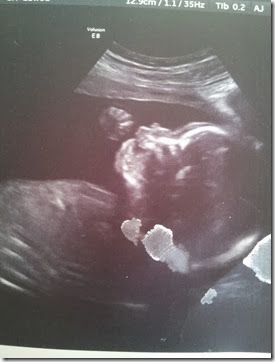

I was also of course excited for them to point out her little girly parts so I can know for sure it is a GIRL!!!

These ultra sound pictures are still so unreal to me! It is crazy how much they can see. They still look a little alienish to me but I think she is just adorable already!! She had her cute little arms up by her face most of the time so this is the best we got!